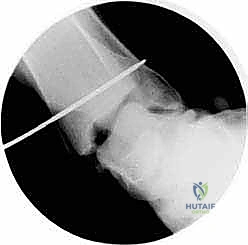

* الأشعة السينية أثناء الوقوف (Weight-bearing X-rays): ضرورية جداً لتقييم الانهيار العظمي، زوايا المفاصل، ومدى ميلان العظم الكاحلي.

2. الفحص بالمنظار (Arthroscopy)

كخطوة أولى، ولضمان الدقة القصوى، غالباً ما يستخدم الدكتور هطيف منظار الكاحل عالي الدقة (4K Arthroscopy). يتم إدخال كاميرا دقيقة جداً عبر شقوق صغيرة (ثقوب) لفحص مفصل الكاحل من الداخل، تنظيف أي أنسجة ملتهبة، ومعالجة أي تلف في الغضاريف قد يكون مصاحباً للإصابة.

5. حفر الأنفاق العظمية وإعادة البناء (Bone Tunnels & Fixation)

هذه هي الخطوة الأكثر دقة هندسياً في الجراحة:

* يتم حفر أنفاق دقيقة جداً في عظمة الكعب الإنسي (قصبة الساق) وفي العظم الكاحلي وأحياناً العظم العقبي، وذلك في نفس نقاط الارتكاز التشريحية للرباط الدالي الأصلي.

* يتم تمرير الطعم الوتري عبر هذه الأنفاق بطريقة تحاكي تماماً شكل ووظيفة الأربطة العميقة والسطحية.

* يتم شد الطعم للدرجة الميكانيكية المثالية التي تضمن استقرار الكاحل دون تقييد حركته الطبيعية.

* يتم تثبيت الطعم بقوة داخل العظام باستخدام مسامير تداخلية (Interference Screws) أو خطاطيف معدنية/بلاستيكية قابلة للامتصاص (Suture Anchors) من أحدث الطرازات العالمية.